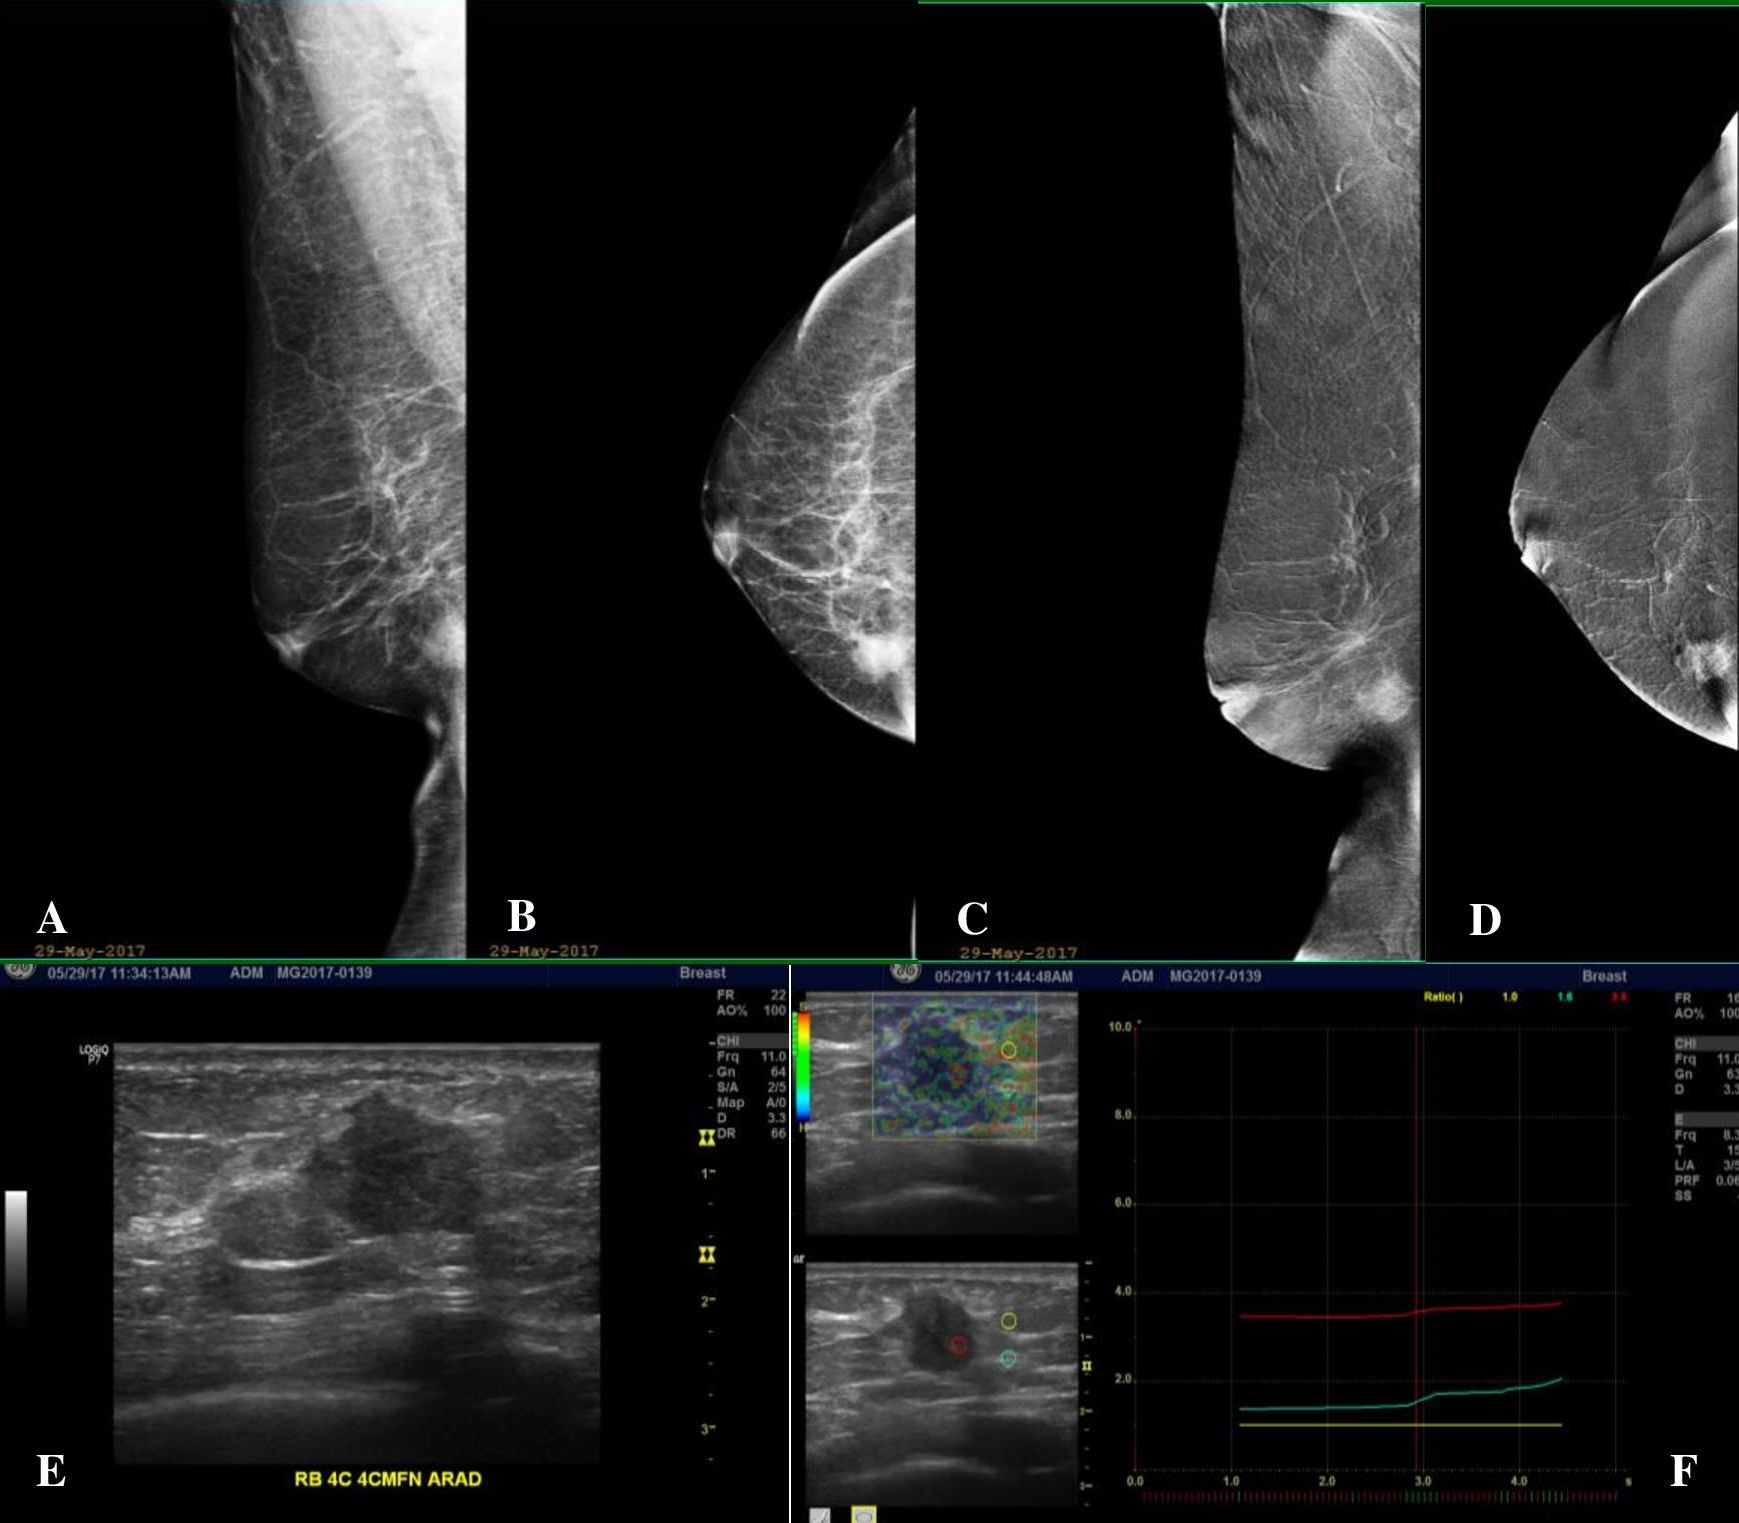

Figure 1. A 63-year-old post-menopausal female with a newly palpable right breast mass with no family history of breast cancer. (A, B) Low-energy (LE) Mediolateral Oblique (MLO) and Craniocaudal (CC) views of the right breast, which has a fatty breast composition, showing an irregular mass of high density at the lower inner quadrant. (C, D) Subtracted images (SI) in MLO and CC projections show avid enhancement of the right lower inner quadrant breast mass. No other abnormal enhancing lesions are demonstrated. The background parenchyma also shows no enhancement. (E) Ultrasound correlate of the said mass shows an irregular markedly hypoechoic solid mass. (F) Elastography (which is a measure of tissue stiffness) shows the mass to be significantly hard compared to the adjacent fat and glandular tissues.